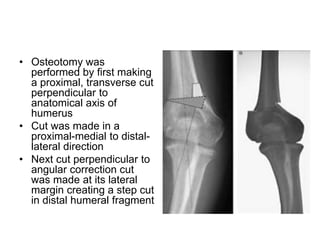

• Osteotomy was

performed by first making

a proximal, transverse cut

perpendicular to

anatomical axis of

humerus

• Cut was made in a

proximal-medial to distal-

lateral direction

• Next cut perpendicular to

angular correction cut

was made at its lateral

margin creating a step cut

in distal humeral fragment